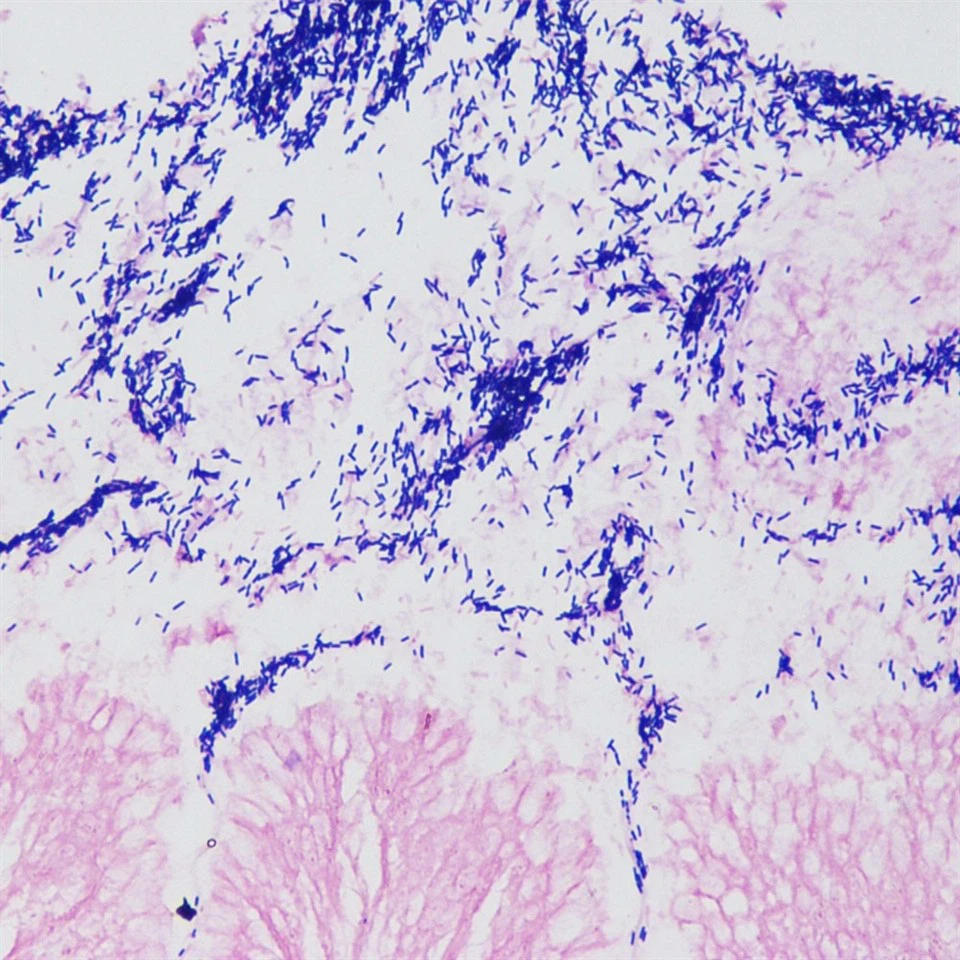

Gramfärgning är en differentiell färgningsmetod som används i stor utsträckning inom mikrobiologin, som kan användas för att skilja grampositiva bakterier (G+) från gramnegativa bakterier (G-). Grundprincipen är baserad på de olika kemiska komponenterna i bakteriecellsväggar. Efter primär färgning med kristallviolett och betningsmedel med jod bildar bakterier vattenolösliga kristallviolett-jodkomplex i cellväggen. Grampositiva bakterier har tjocka cellväggar, innehåller inga lipider, är rika på peptidoglykan och är tvärbundna för att bilda en tät rutnätsstruktur. När det behandlas med etanol, krymper peptidoglykannätet, vilket kan blockera kristallviolett-jodkomplexet. Det finns kvar i cellväggen, vilket ger den lila färgen av kristallviolett. Gramnegativa bakterier har å andra sidan tunna cellväggar, låg peptidoglykanhalt och lös tvärbindning. När det utsätts för etanol löses det lipidrika yttre membranet upp, en stor lucka uppstår i cellväggen och kristallviolett-jodkomplexet rinner ut, så att cellerna blir färglösa efter etanolavfärgning. Vid denna tidpunkt kommer gramnegativa bakterier att färgas röda genom safraninmotfärgning.

Gramfärgningslösning innehåller fyra komponenter, nämligen ammoniumoxalat kristallviolett färgningslösning, 1 % jodlösning, avfärgningslösning och fuchsinfärgningslösning. Efter färgning verkar grampositiva bakterier lila till blålila och gramnegativa bakterier ser röda ut.